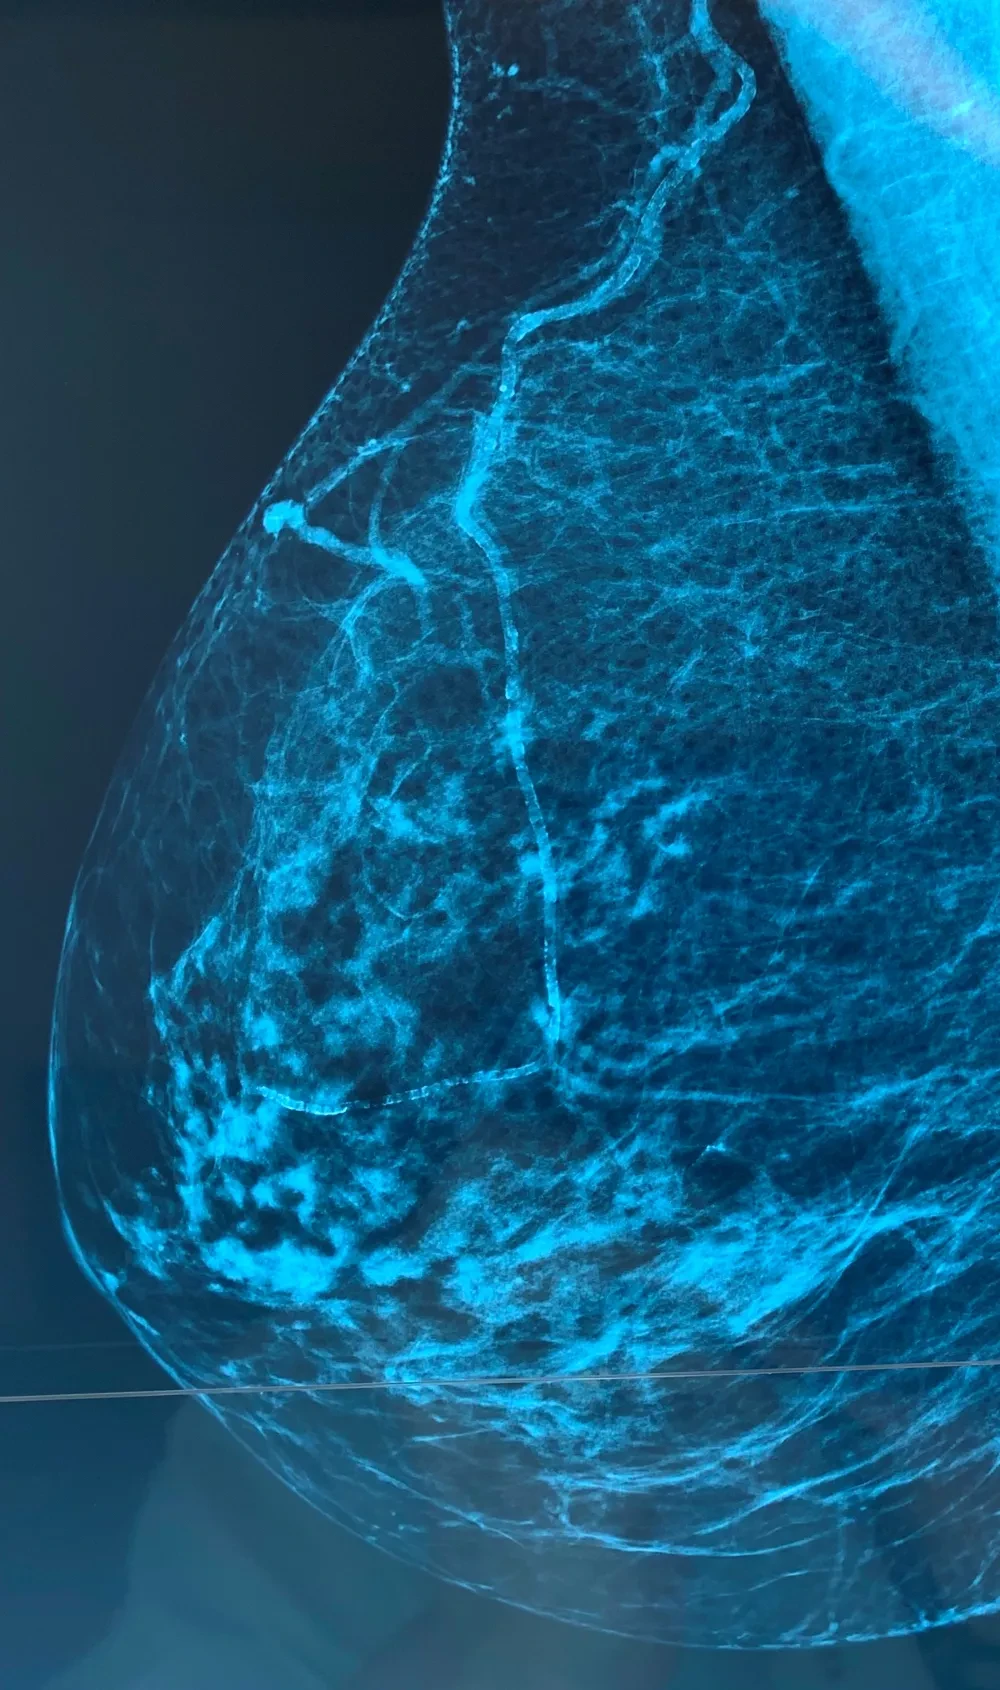

L'identification des calcifications carotidiennes et fémorales comme marqueur du risque CV est très antérieure au CAC (score coronaire calcique) et elle est fiable. On peut y associer les calcifications de l'aorte sous rénale et définir ainsi un score de risque CV chez les patients en prévention primaire et donc alors d'ajuster le LDL et prescrire ou non une statine. Bien entendu dans ce contexte en cas de score > 4 une consultation cardiologique s' impose suivi ou non d'un score calcique coronaire qui se transforme de plus en plus en coronaroscanner, qui va devenir un outil en prévention CV primaire. C'est déjà le cas et de plus en plus. De même on va prescrire une angio scanner des artères des MI devant un IPS à 0.80 chez un patient asymptomatique..........................telle est la médecine d'aujourd'hui qui se cristallise essentiellement sur la paraclinique donc les images, c'est normal car la clinique est de sortie .....pas partout heureusement, mais ça progresse !

Lz rôle prédictif des calcifications carotidiennes est reconnu vs CAC . Mais dans la pratique ces plaques carotidiennes ne suffisent pas à mon sens et j'ajoute les plaques du segment iliofémoral droit et gauche et les plaques au niveau de l'aorte sous-rénale. Enfin les calcifications mammaires sont aussi très utiles. Cette comptabilisation est simple, les plaques à retenir doivent être au minimum de 2 mm d'épaisseur . Dans la VRAIE VIE les patients concernés sont tous à haut risque CV. Il faut privilégier le NON INVASIF en prévention primaire ! Enfin ne pas oublier que tout cela doit être précédé de la correction "drastique" des FDRCV, sinon à quoi bon vouloir faire une prévention primaire. Evaluer le risque CV en prévention primaire, c'est aussi mesurer l'onde de pouls , l'épaisseur intima média et l'IPS de cheville. C'est ainsi que l'on peut détecter un risque CV significatif chez un patient jeune asymptomatique et alors prescrire une statine en fixant la cible LDL en tenant compte de tous ces paramètres. C'est cost-effective, c'est efficace, ça prend peu de temps et ainsi le cadrage vasculaire du patient est complet. La consultation cardiologique sera systématique.

J'évalue score calcique artériel périphérique depuis 20 ans , je l'appareille aux FDRCV classiques, et le LDL . PLus récemment j'y associe la Lp(a). Ainsi la prévention primaire CV est optimisée et efficace.